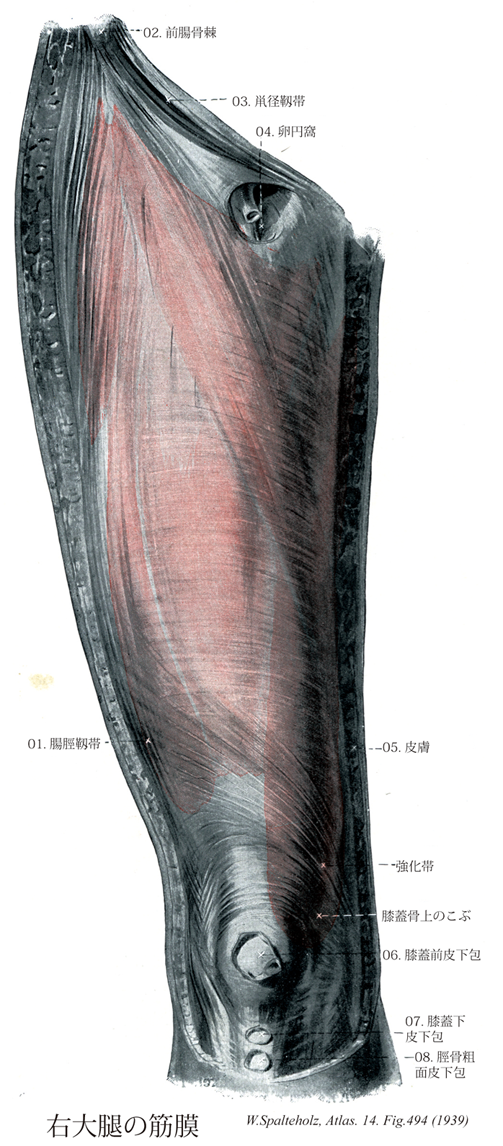

Spalteholz HANDATLAS DER ANATOMIE DES MENSCHEN VON WERNER SPALTEHOLZ

494

Maissiat, Bandelette of

- 494_01Maissiat, Bandelette of【Iliotibial tract腸脛靱帯 Tractus iliotibialis】 Vertically oriented lateral thickening of the fascia lata extending from the anterior part of the iliac crest to the lateral condyle of the tibia. It receives fibers from the tensor muscle of the fascia lata and the gluteus maximus.

→(腸脛靱帯は大腿筋膜の補強層として腸骨稜から大腿外側を下行し、股関節と膝関節をこえて脛骨外側顆に至る。大腿筋膜張筋、大腿筋、中臀筋の腱性線維から起こり、脛骨への停止以外では、外側筋間中隔を介して大腿骨に付着する。また、腓骨頭や外側膝蓋支帯への線維もある。腸脛靱帯は大腿骨の牽引帯である。立脚期には体重が大腿骨を内側にくぼませる曲げの力として働く。腸脛靱帯の緊張は大腿骨を逆方向に曲げる力を生じ、大腿骨内側に加わる圧力と外側に加わる張力を大きく軽減する。中臀筋の収縮は骨盤の落込みを防ぐとともに腸脛靱帯を緊張させ、支持脚側への荷重が増すにしたがって牽引帯としての作用を発揮させる。)

- 494_02【Anterior superior iliac spine; Iliospinale anterius上前腸骨棘;前腸骨棘 Spina iliaca anterior superior; Spina ilica ventralis】 Bony projection at the anterior border of the iliac crest giving origin to the sartorius muscle.

→(腸骨稜の前端は鈍円な突起として大きく突出し、上前腸骨棘として体表上からもよく触れる。大腿筋膜張筋および縫工筋が起こる。)

- 494_03Fallopian ligament; Poupart's ligament; Vesalius' ligament【Inguinal ligament鼡径靱帯;鼡径弓 Ligamentum inguinale; Arcus inguinalis】 Inferior end of the aponeurosis of the external oblique. It passes from the anterior superior iliac spine to the pubic tubercle.

→(鼡径靱帯は上前腸骨棘と恥骨結節との間に張る靱帯で、前面における体幹と下肢の境界である。外腹斜筋の停止腱膜のつくる腱弓の発達したものである。恥骨櫛は恥骨結節のやや後部から後外側にのびているので、鼡径靱帯は恥骨櫛よりもやや前方にある。鼡径靱帯の内側端の一部は分かれて後走し、恥骨櫛は恥骨結節のやや後部から後外側にのびているので、鼡径靱帯は恥骨櫛よりもやや前方にある。鼡径靱帯の内側端の一部は分かれて後走し、恥骨櫛内側部に達する。これを裂孔靱帯といい、鼡径管下壁の形成に関与する。裂孔靱帯外側縁が恥骨櫛に沿ってのびているものを恥骨櫛靱帯という。また、浅鼡径輪の外側脚をを作る外腹斜筋腱膜線維が鼡径靱帯内側端に到達した後、上内側に方向をかえて反転し、腹直筋鞘前葉をつくる内腹斜筋の前面に向かって線維を送る。これを反転靱帯といい、鼡径管内側端に到達した後、上内側に方向をかえて反転し、腹直筋鞘前葉をつくる内腹斜筋の前面に向かって線維を送る。これを反転靱帯といい、鼡径管内側端で、その後壁の形成に関与する。プーパルの靱帯とも呼ばれる。Poupart, Francois (1616-1708)フランスの外科医、ルイ14世の侍医。プーパルの靱帯(鼡径靱帯)を既述("Suspenseurs del'-abdomen", Hist. Acad. Roy. Sci., Paris, 1730, 51)、プーパル線は鼡径靱帯の中心と鎖骨とを結ぶ線。)

- 494_04【Saphenous opening伏在裂孔;卵円窩 Hiatus saphenus; Fossa ovalis】 Large aperture in the fascia lata just below the inguinal ligament for the passage of the great saphenous vein.

→(BNA,INAでは卵円窩とも呼ばれていた。大腿の前面上部にある大腿筋膜の欠損部で、鼡径靱帯内側端の下方にある。大伏在静脈が大腿静脈に合する直前でこれを通過する。裂孔の周縁をつくる大腿筋膜は肥厚して内側に向いたC字形を示し、その上縁を上角、下縁を下角といい、また両者の中間部を鎌状縁という。伏在裂孔の内側部では、大腿筋膜はその深層の恥骨筋膜に移行して裂孔の床をつくるが、この部はリンパ管や血管によって貫かれて網状を呈し、これを篩状筋膜という。)

- 494_05【Skin皮膚 Cutis】 Collective term for the epidermis and dermis.

- 494_06【Subcutaneous prepatellar bursa膝蓋前皮下包;皮下膝前包 Bursa subcutanea prepatellaris】 Bursa situated directly between the skin and the fascia anterior to the knee.

- 494_07【Subcutaneous infrapatellar bursa膝蓋下皮下包;膝下皮下包 Bursa subcutanea infrapatellaris; Bursa infrapatellaris subcutanea】 Bursa situated between the patellar ligament and the skin.

- 494_08【Subcutaneous bursa of tuberosity of tibia脛骨粗面皮下包 Bursa subcutanea tuberositatis tibiae】 Bursa situated between the tibial tuberosity and the skin. Bursa most stressed by kneeling.